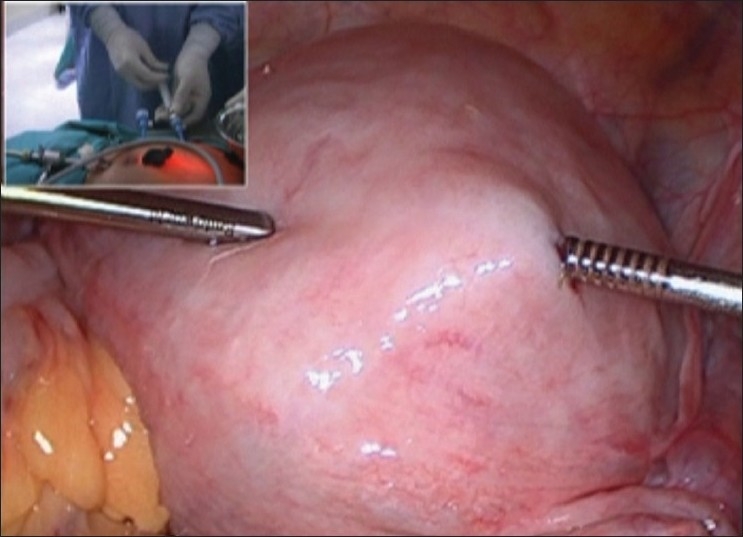

本研究的目的是评估水剥技术在子宫肌瘤切除术中减少失血量的效果,并评估使用倒钩缝线缝合子宫肌瘤缺损的益处和可行性。抗利尿激素用生理盐水稀释,每100毫升生理盐水稀释10单位抗利尿激素。对于8cm大小的肌瘤,用400ml生理盐水稀释40单位抗利尿激素。将400ml的生理盐水全部注射到肌层中。用简单的剪刀在子宫上切开(不需要能量源)。当子宫被切开时,发生的不是出血,而是生理盐水渗漏。这有助于保持视野清晰,并且更容易在肌瘤和肌层之间找到正确的平面。由于生理盐水注射对正确平面的剥离,有助于肌瘤的分离。

The objective of this study was to evaluate the efficacy of aquadissection technique to reduce the blood loss in myomectomy and to assess the benefits and feasibility of the use of barbed suture for myometrial defect closure. Vasopressin is diluted with saline as 10 units of vasopressin for every 100 ml of saline. For a fibroid of about 8 cm size, 40 units of vasopressin is diluted in 400 ml of normal saline. The whole of 400 ml of this saline is injected in the myometrium. Incision is made on the uterus with just simple scissors (no energy source is required). As the uterus is cut, instead of bleeding, saline leakage takes place. This helps to keep the field clear and it is easier to get the correct plane between the fibroid and the myometrium. The separation of the fibroid is helped due to the dissection of the correct plane by the saline injection.